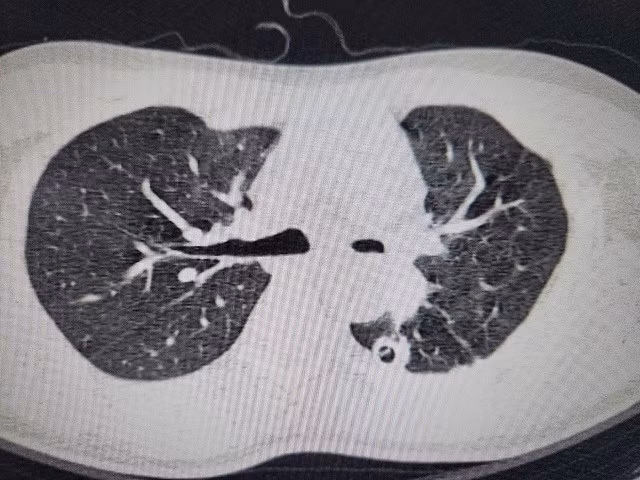

| Hình ảnh phim chụp hẹp phế quản gốc trái, xẹp hoàn toàn phổi trái do di chứng của lao phổi - Ảnh BVCC |

Anh B được chuyển đến Khoa Phẫu thuật Lồng ngực, Bệnh viện Bạch Mai. Qua các thăm khám lâm sàng và chụp chiếu, kết quả quả cho thấy, anh B đối diện với nguy cơ mất phổi vĩnh viễn: Chụp CT 3D phổi cho thấy phế quản gốc trái chỉ còn khe hẹp 2mm, phổi xẹp đặc như tấm bìa cứng. Nếu không phẫu thuật trong 2 tuần, phổi sẽ hoại tử.